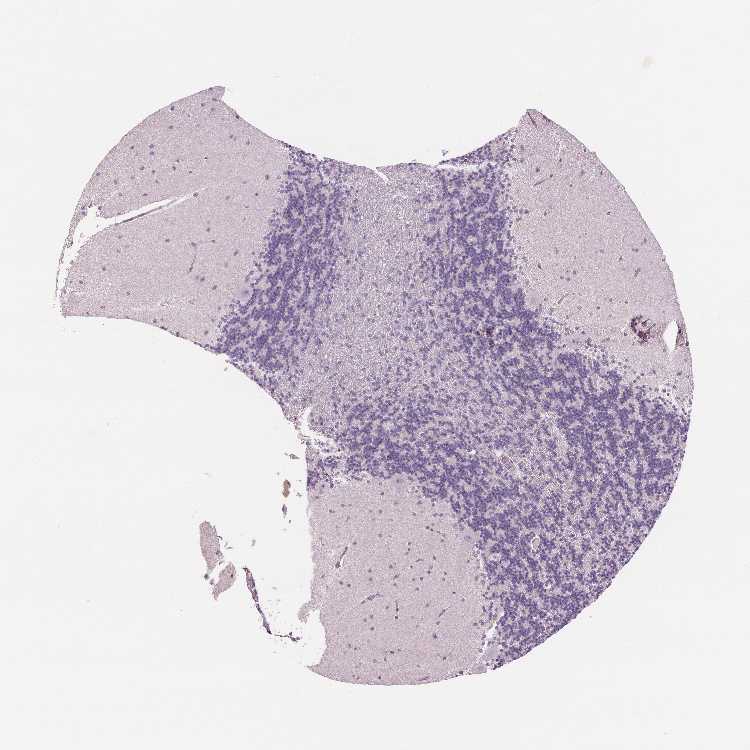

CEREBELLUM - Antibody stainingi

Antibody staining in the annotated cell types in the current human tissue is reported as not detected, low, medium, or high, based on conventional immunohistochemistry profiling in selected tissues. This score is based on the combination of the staining intensity and fraction of stained cells.

Each image is clickable and will lead to virtual microscopy that enables deeper exploration of all samples and also displays staining intensity scores, fraction scores and subcellular localization as well as patient and tissue information for each sample.

Antibody HPA063613

Purkinje cells Not detected

Cells in granular layer Not detected

Cells in molecular layer Not detected